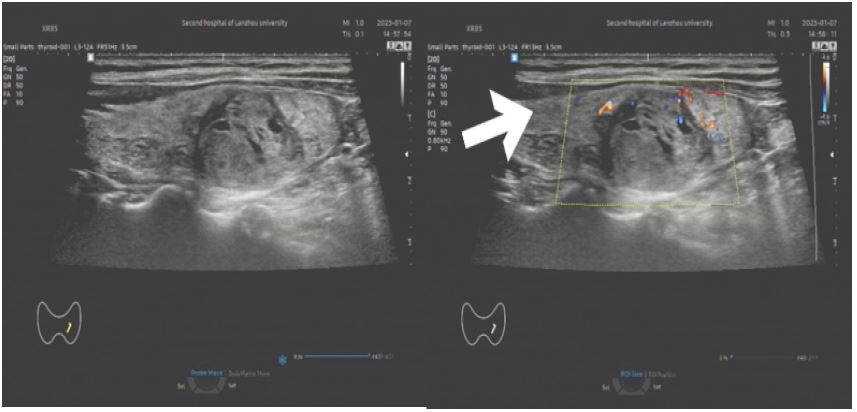

Imaging findings: Ultrasound revealed multiple mixed-echo nodules in both thyroid lobes: Left lobe: 2.2×1.7 cm (predominantly solid); Right lobe: 2.7×1.9 cm (predominantly solid).

Features: aspect ratio <1, regular shape, well-defined margins, peripheral and intranodular vascularity (C-TIRADS 3). Contrast-enhanced neck CT suggested nodular goiter with multiple adenomas.

Figure 2: (A) a cystic solid mass of about 2.2 x 1.7 cm in size is seen in the left lobe of the thyroid gland (shown by arrows), with a regular morphology, clear borders, uneven internal echogenicity, and a hypoechoic halo is seen around it; (B) a small amount of short rod-shaped blood flow signals can be seen inside and around the mass (shown by arrows).